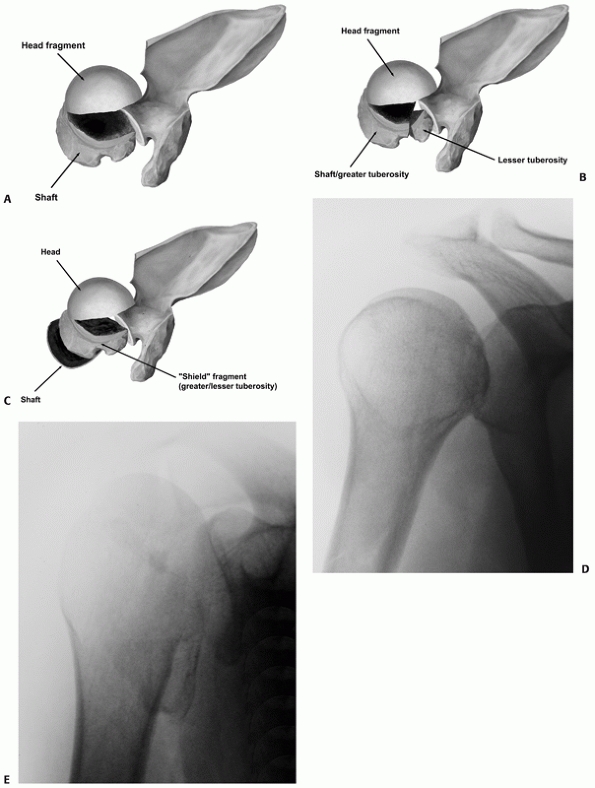

FIGURE 35-16

The tuberosity fracture configuration in threeand four-part fractures follows three common configurations on anteroposterior, modified axial, and three-dimensional computed tomography reconstructions. In a three-part greater tuberosity fracture, the primary fracture line (black arrow) is always located posterior to the bicipital groove (white arrow) on the modified axial view (A,B). In a four-part fracture, there is in addition a composite shield fragment consisting of the lesser tuberosity, the bicipital groove (gray arrow), the anterior portion of the greater tuberosity (black arrow), and frequently an adjacent marginal portion of the articular surface (white arrows), as shown on these three-dimensional computed tomography reconstructions (C,D). The shield fragment may be comminuted or “shattered,” leading to a more characteristic four-part fracture configuration. In this case, the three-dimensional reconstructions show at least three separate fractured components of the shield (arrow) (E,F). |